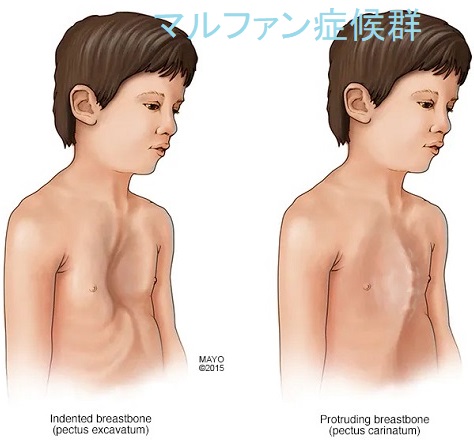

マルファン症候群(marfan syndrome:MFS)は、常染色体優性遺伝性の結合組織異常。フィブリリン-1(fibrillin-1)をコードするFBN1遺伝子やTGF-β 受容体遺伝子の突然変異により、過剰TGF-βの臓器沈着からコラーゲン形成障害が生じます。

マルファン症候群の身体的特徴として、高身長で四肢の指が長い、胸郭の変形、眼の水晶体亜脱臼などがあります。

マルファン症候群で特に問題になるのが大動脈壁の脆弱性で、

通常の急性大動脈解離は60歳以上の高齢者に多い病気ですが、マルファン症候群では20歳-30歳代で発症することが多い。